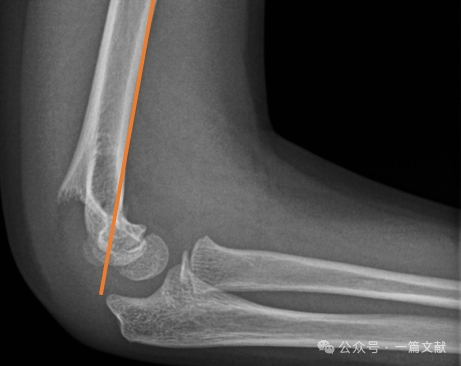

Alignment on Lateral Radiograph:

* Anterior Humeral Line (AHL): Should pass through the ossification center of the capitellum.

* Capitellar Anterior Angle: 30-40 degrees.

* Lateral Capitellohumeral Angle (LCHA): Should be less than 69 degrees.

* Posterior Fat Pad Sign: Highly suggestive of fracture (whereas an anterior fat pad sign can be seen without fracture).